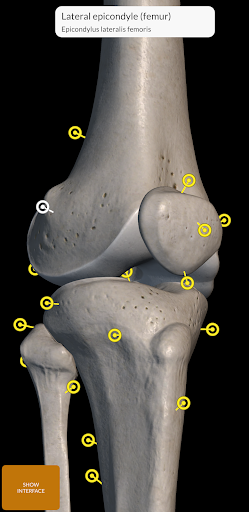

Mỗi xương của bộ xương người đã được tái tạo ở dạng 3D, bạn có thể xoay và phóng to từng mô hình và quan sát chi tiết từ mọi góc độ.

Bằng cách chọn mô hình hoặc ghim, bạn sẽ được hiển thị các thuật ngữ liên quan đến bất kỳ bộ phận giải phẫu cụ thể nào, bạn có thể chọn từ 12 ngôn ngữ và hiển thị các thuật ngữ bằng hai ngôn ngữ cùng lúc.

• Bề mặt của bộ xương có kết cấu độ phân giải cao lên đến 4K

• Xoay và Phóng to mọi mô hình trong không gian 3D

• Ghim tương tác cho phép trực quan hóa thuật ngữ liên quan đến mọi chi tiết giải phẫu